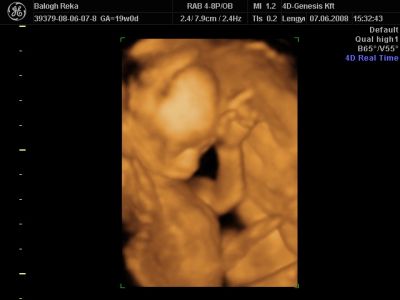

Huhh, hát annyira jó élmény volt, most tök boldog vagyok! Nagyon örülök, hogy mégis elmentem mégegyszer, mert sokat vacilláltam ám. A 4D Genesis egyszerűen szuper, mindenkinek nagyon nagyon tudom ajánlani, ezen belül is engem a Lengyel Györgyné Márti fogadott. Szuper ez a nő, akkora átéléssel és profizmussal csinálta az egész vizsgálatot! Mindent részletesen megnézett, megmutatott, elmagyarázott, nem sajnálta az időt. A felvétel gyönyörű lett, az egész baby nagyon szépen látszik, végig fent volt és mocorgott, hihetetlen aranyos volt, és nagyon szép!

Bemutatott párszor, ezek mind meg is vannak örökítve!

Na és a lényeg...jöjjenek a sztárfotók! Bocsi előre, 8 lesz és kicsit nagyok, de nem tudtam választani, azokat a bemutatásokat mind muszáj volt felraknom, tök vicces!